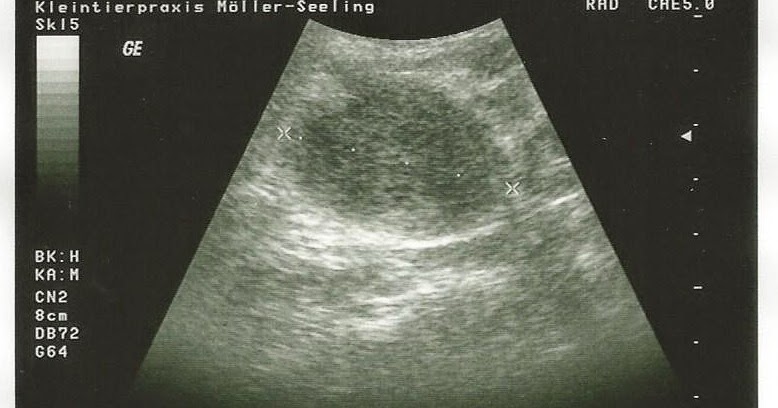

Vettie Notizen einer Wetterauer Tierärztin Mein Hund hat Krebs und

Ria und der dicke Bauch Hunderunden